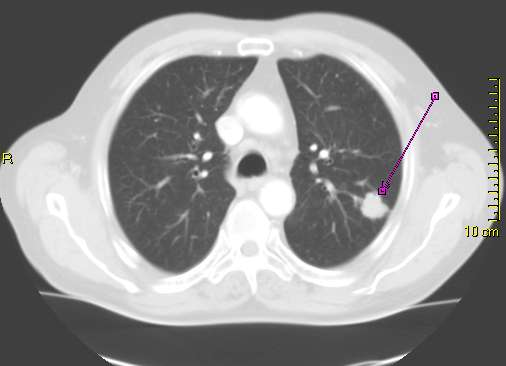

- Beschreibung: Kleiner Lungentumor ( T1) linker Oberlappen